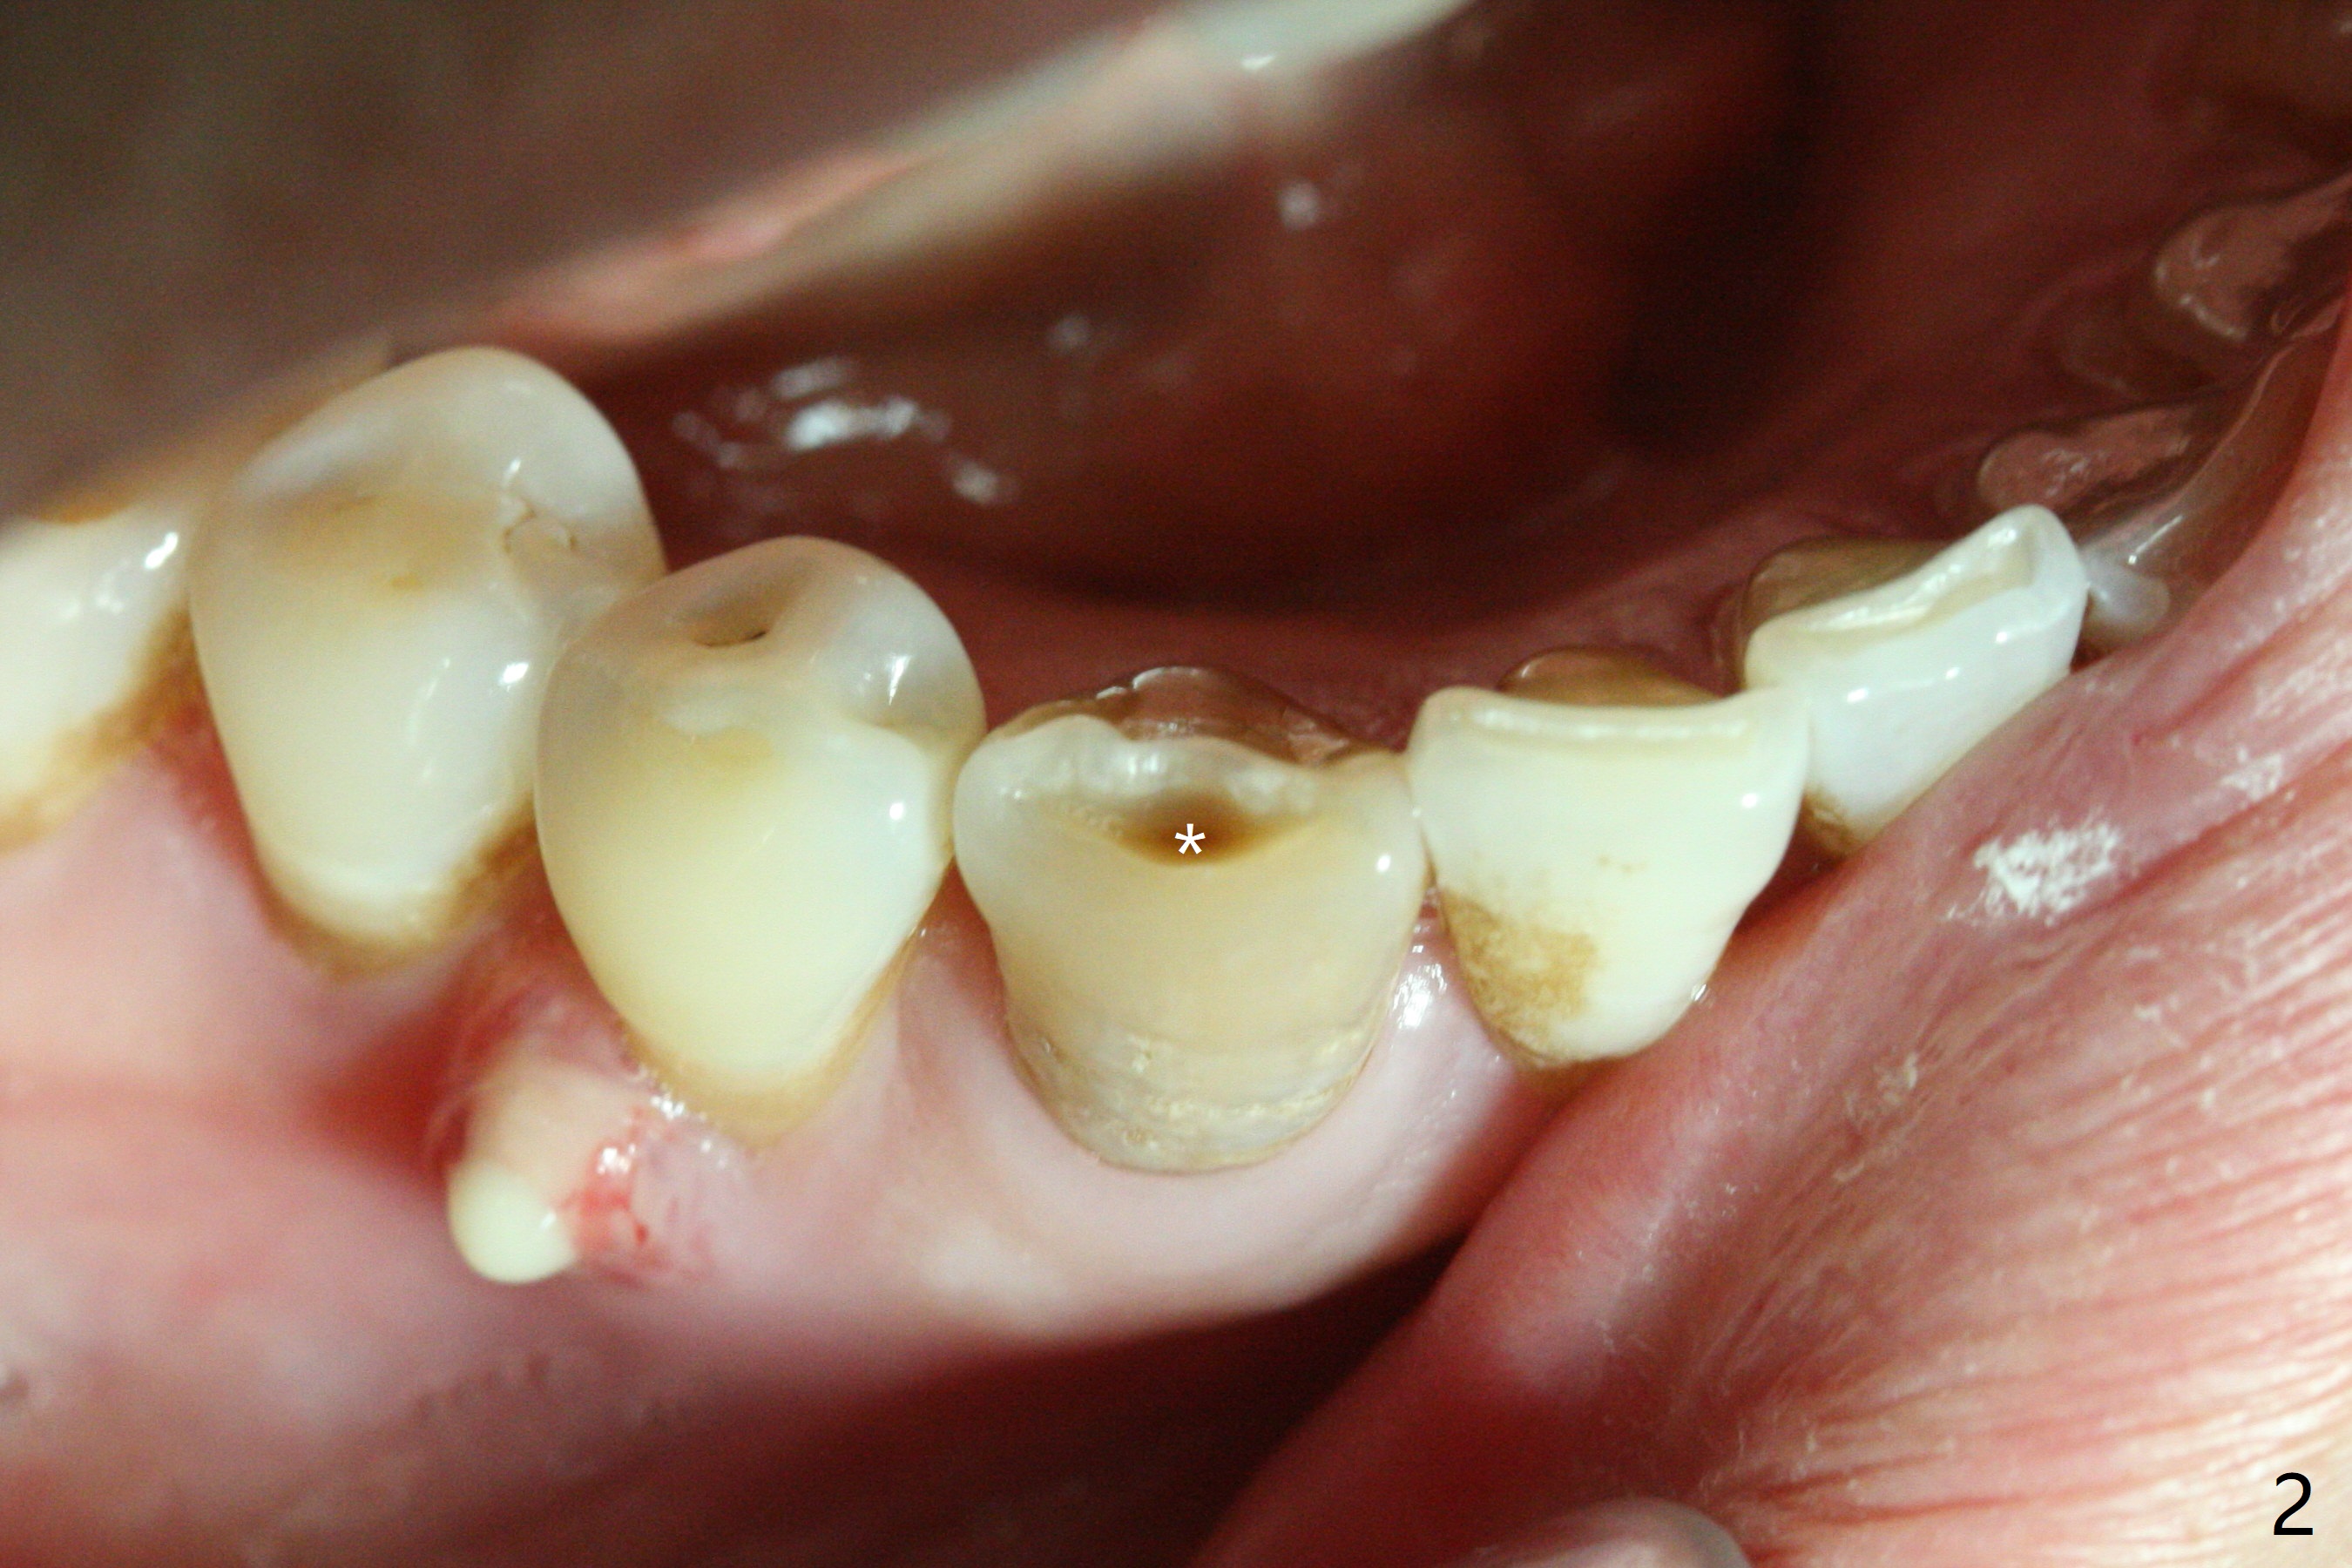

A 47-year-old woman with autoimmune hepatitis has a fistula distal to the tooth #28, but the tooth #27 is discolored and necrotic (pulpal test: 28 vital, Fig.1) with an incisal dimple (wear facet, Fig.2). Periapical radiolucency appears to involve the teeth #27 and 28. RCT is initiated at #27 through the incisal dimple. The orifice is reached immediately. Occasionally Sodium Hydro chlorite solution seems to leak out of the fistula. After debridement and placement of Ca(OH)2 paste (Fig.4 *) in the canal, the fistula is apparently shrunken (data not shown). The patient is scheduled to return 1 month.